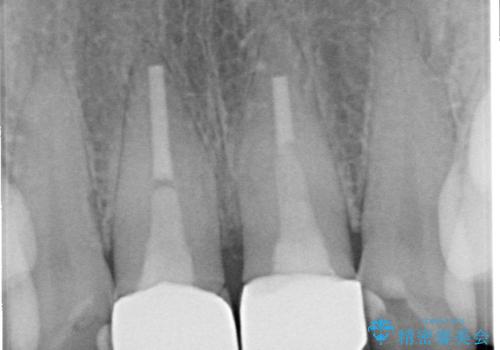

- 前歯の色が黄色くなって気になるとのことで来院された患者様です。

約20年前に前歯の根管治療を行い、保険の被せものを入れたとのことです。

拡大鏡視野下で、被せもの、金属の土台、虫歯を除去し、ファイバーの土台(ファイバーコア)をたてて、オールセラミッククラウンに適した形に整えました。

根管治療をご提案しましたが、患者様のご希望で行っておりません。